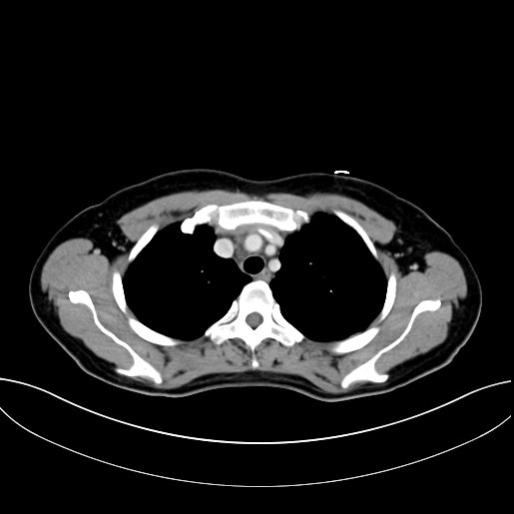

1.胸部增强CT(2013-02-06 **市院):前纵隔占位,考虑淋巴瘤可能大,侵及周围血管及心包,心包及双侧胸腔少量积液,双侧心膈角旁淋巴结增大。(附图)

化疗前患者胸闷,不能平卧,第一疗程第6天胸闷缓解,可平卧。第10天复查CT提示纵隔肿块明显缩小。

胸腹部CT(2013-06-04,本院):1)右肺中叶内侧段陈旧性病灶。2)两肺间质性改变。3)心包少量积液。4)肝肿大,肝脏右叶小血管瘤。5)胆囊炎。6)子宫体部病灶,考虑子宫肌瘤。7)盆腔少量积液。(附图)

评估:CR。